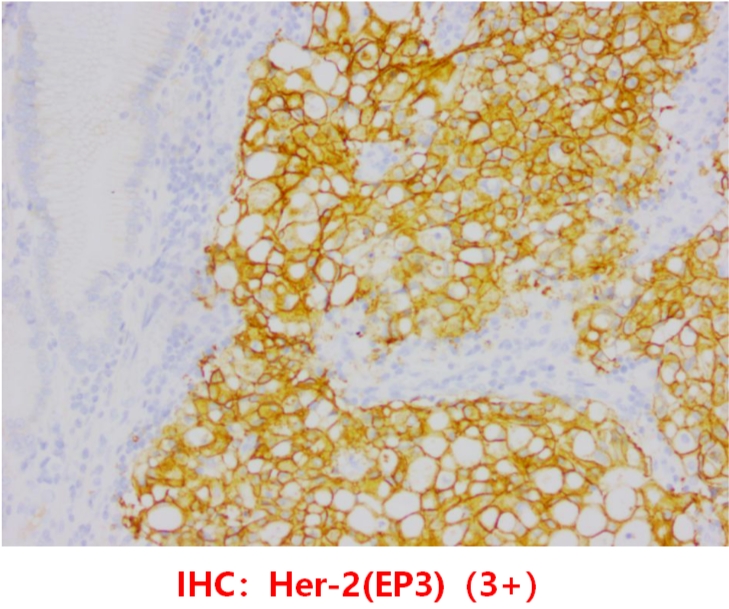

MSH2(+),MSH6(+),MLH1(+),PMS2(+),CK(pan)(+),HER2(EP3)(3+)